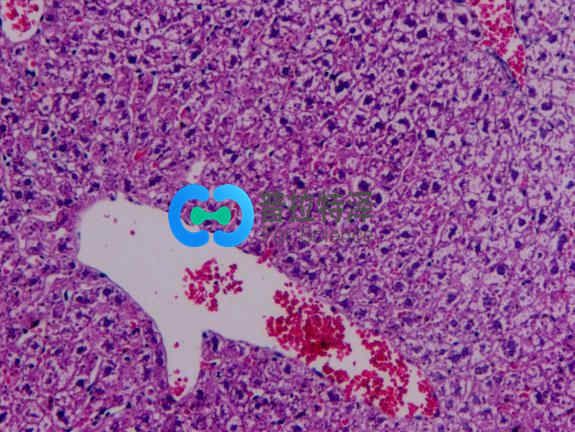

非酒精性脂肪性肝病(NAFLD)是一種無酒精濫用的肝病綜合征,包括單純性脂肪肝、脂肪性肝炎、脂肪性肝纖維化和肝硬變。可從單純性脂肪肝經(jīng)非酒精性脂肪性肝炎(NASH)發(fā)展為肝纖維化,甚至導(dǎo)致肝硬化、肝細(xì)胞癌(HCC)或肝功能衰竭等終末期肝病。

給予動(dòng)物高脂、高糖飼料喂養(yǎng)建立的脂肪肝模型,其主要發(fā)病機(jī)制是營養(yǎng)過剩,食物中脂類、膽固醇和(或)糖類過量,無法完全吸收利用,脂類堆積于肝而引發(fā)脂肪肝,進(jìn)一步出現(xiàn)肝炎性改變及纖維化。該模型與人類NAFLD 相似,是最常見的NAFLD動(dòng)物模型。不同的飲食誘導(dǎo)模型具有不同的特點(diǎn)。飲食誘導(dǎo)模型的一個(gè)挑戰(zhàn)可能是在開始研究之前需要較長的時(shí)間造模。

小劑量鏈脲佐菌素結(jié)合高脂飲食,已被用于制備小鼠的NAFLD,可導(dǎo)致脂肪變性,炎癥,纖維化甚至肝細(xì)胞癌。四氯化碳(CCl4)可造成肝損傷,可單獨(dú)施用或配合高脂飲食來誘發(fā)脂肪肝或肝纖維化。其機(jī)制主要是CCl4誘導(dǎo)肝臟發(fā)生氧化應(yīng)激反應(yīng),導(dǎo)致有害的脂質(zhì)和蛋白質(zhì)過氧化產(chǎn)物不斷產(chǎn)生和積累,并發(fā)生嚴(yán)重的壞死反應(yīng),從而導(dǎo)致肝細(xì)胞結(jié)構(gòu)和功能破壞。這種方法造模時(shí)間較短,但是發(fā)病機(jī)制、病程變化及組織學(xué)形態(tài)與人類脂肪肝存在較大差異,并且藥物毒性強(qiáng),易致動(dòng)物死亡。